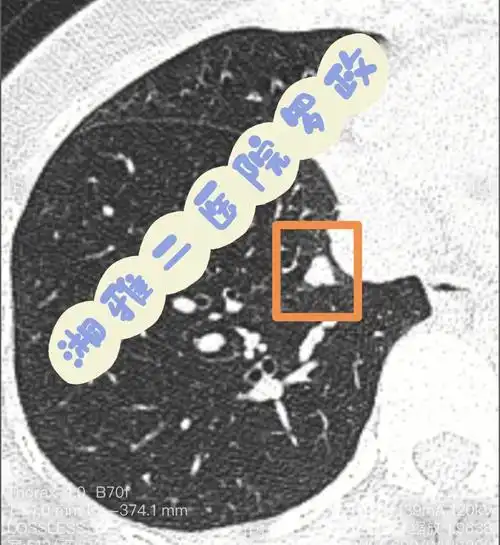

1cm经我影像诊断有最后手术病理的肺结节